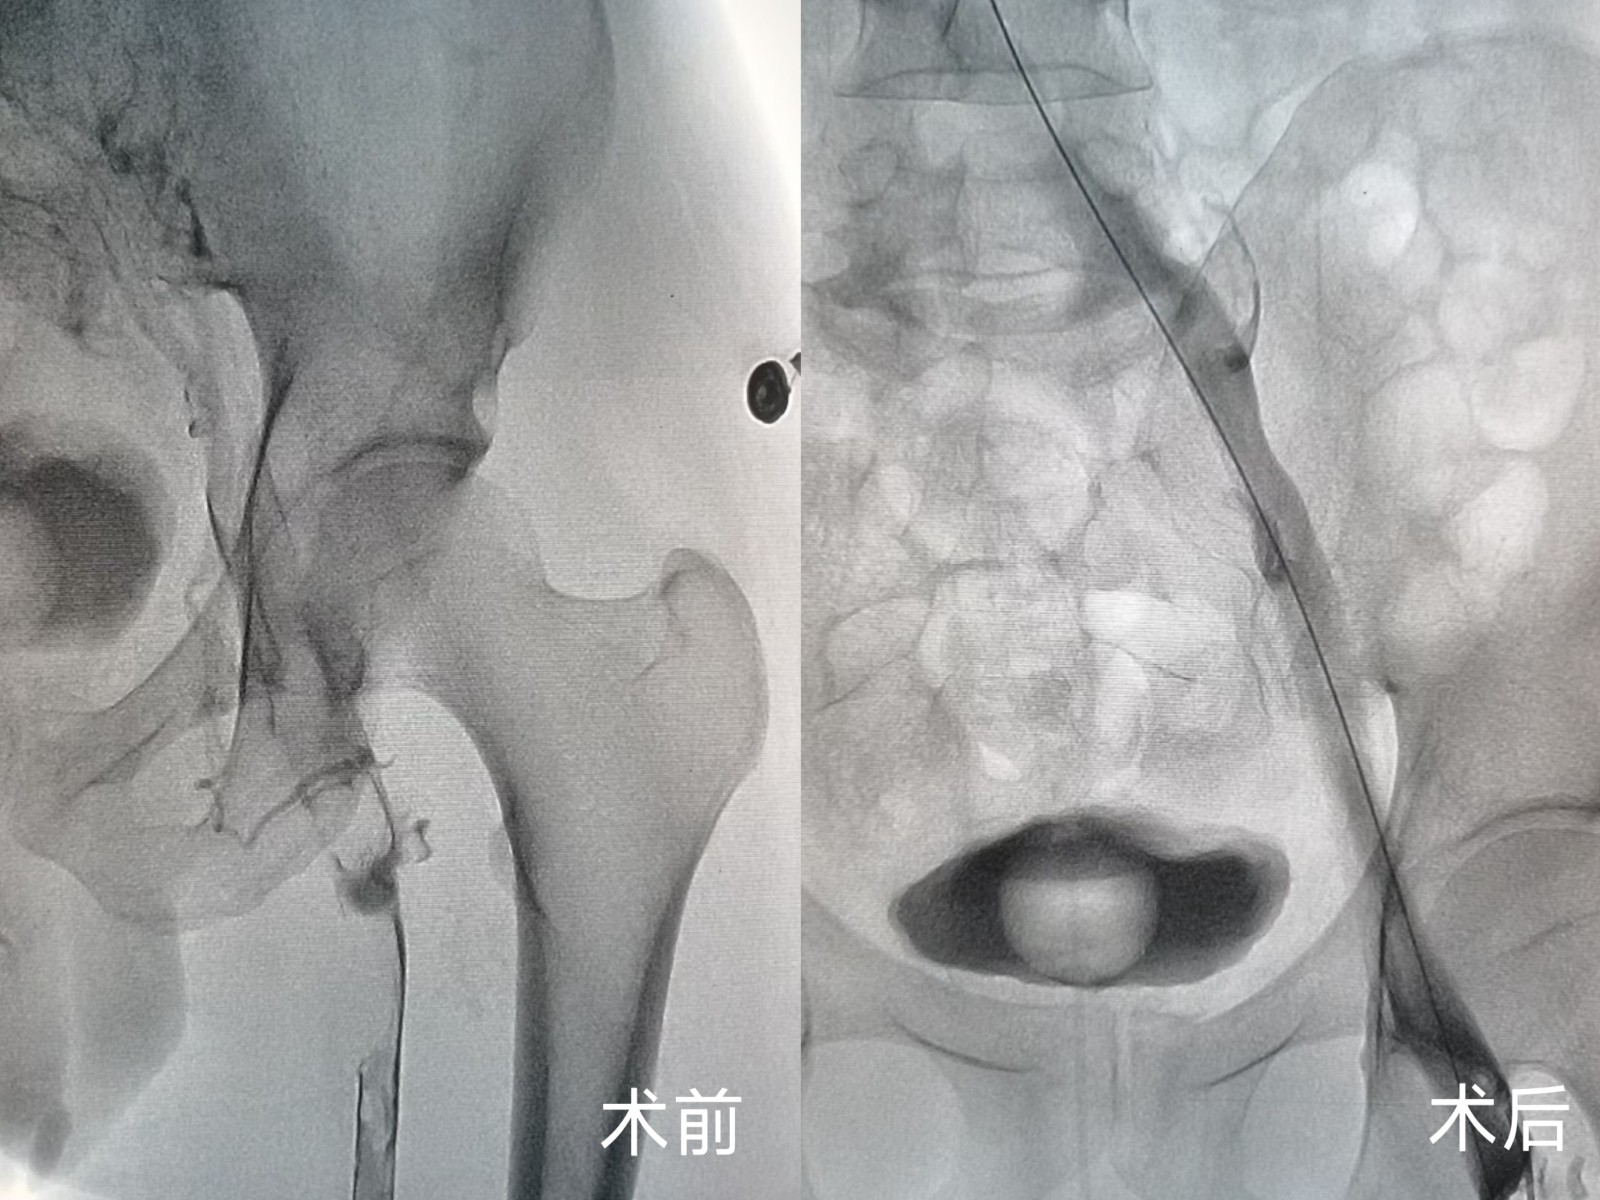

无独有偶,一位左下肢突发肿胀伴剧烈疼痛的患者,在症状出现仅1天后便慕名前来求医。患者病情进展迅速,肢体肿胀明显,疼痛难忍,严重影响正常行走。科室团队快速响应,经详细检查后明确诊断为左下肢深静脉血栓,随即为患者安排紧急手术。术中,团队先为患者置入滤器预防肺栓塞,再运用同款外周静脉取栓支架系统,精准、高效地清除了下肢静脉内的血栓。

术后即刻,患者左下肢疼痛症状明显缓解,肿胀程度显著减轻,术后恢复期间,肢体功能逐步恢复正常,患者对治疗效果赞不绝口。